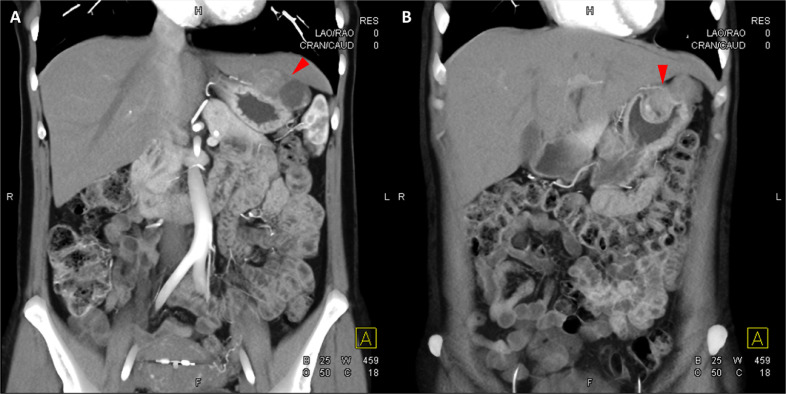

胸部、腹部和骨盆的对比增强动脉和静脉期 CT 显示多个圆形、主要是血管丰富的异质肿块,具有囊性和实性成分,起源于胃底和胃体(图 2-4)。 病变部分呈外生结构,被认为位于粘膜下层。 在颈部多发同步性副神经节瘤的情况下,最初的鉴别诊断包括多发性副神经节瘤、多发性 GIST 以及转移性疾病。